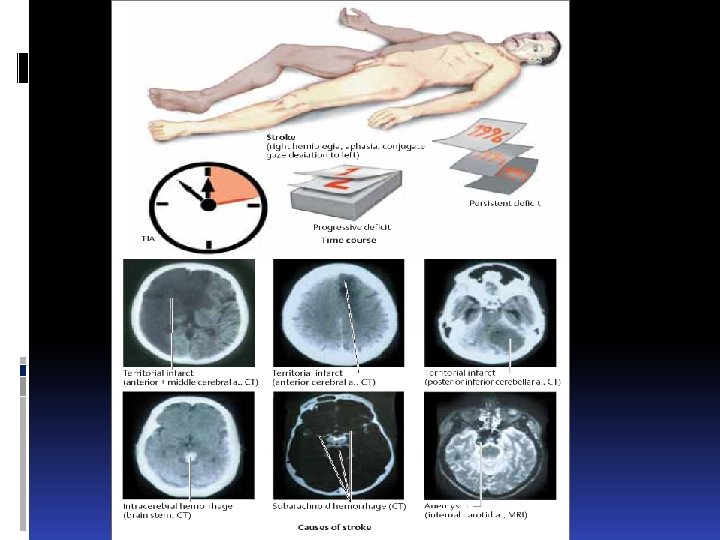

The Contents to lectures: Stroke A stroke is an acute focal or global impairment of brain function resulting from a pathological process (e. g. thrombus, embolus, vessel rupture) of the blood vessels. Its causes, in order of decreasing frequency, are ischemia (80%), spontaneous intracerebral or intraventricular hemorrhage (15%), and subarachnoid hemorrhage (5 %). The signs and symptoms of stroke are usually not specific enough to enable identification of its etiology without further diagnostic studies. CT, MRI, cerebrovascular ultrasonography, ECG, and laboratory testing are usually needed.

The Contents to lectures: Stroke A stroke is an acute focal or global impairment of brain function resulting from a pathological process (e. g. thrombus, embolus, vessel rupture) of the blood vessels. Its causes, in order of decreasing frequency, are ischemia (80%), spontaneous intracerebral or intraventricular hemorrhage (15%), and subarachnoid hemorrhage (5 %). The signs and symptoms of stroke are usually not specific enough to enable identification of its etiology without further diagnostic studies. CT, MRI, cerebrovascular ultrasonography, ECG, and laboratory testing are usually needed.

Types of infarct. There are three basic types of brain infarct, distinguished from each other by the caliber of the occluded arteries: Territorial infarcts are mainly produced by occlusions of the main trunks or major branches of cerebral arteries (cerebral macroangiopathy), which may be due to thrombosis, embolism, or other causes. The infarct includes both cortex and subcortical white matter and sometimes the basal ganglia and thalamus (Fig. 6. 12). It is usually possible to infer which vessel has been occluded from the pattern of neurological deficits that are produced.

Types of infarct. There are three basic types of brain infarct, distinguished from each other by the caliber of the occluded arteries: Territorial infarcts are mainly produced by occlusions of the main trunks or major branches of cerebral arteries (cerebral macroangiopathy), which may be due to thrombosis, embolism, or other causes. The infarct includes both cortex and subcortical white matter and sometimes the basal ganglia and thalamus (Fig. 6. 12). It is usually possible to infer which vessel has been occluded from the pattern of neurological deficits that are produced.